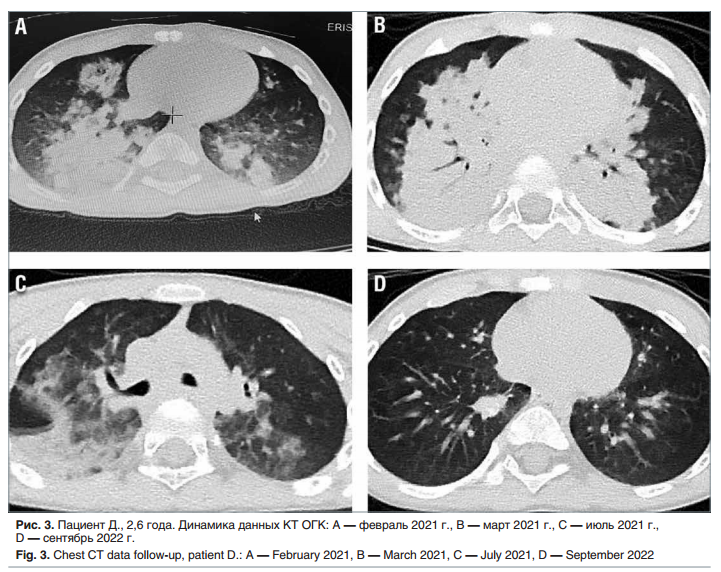

На фоне терапии в течение 13 мес. (июль 2021 г. — сентябрь 2022 г.) одышка и кашель купировались, подъемов температуры тела не отмечалось. ОАК, общий анализ мочи, биохимический анализ крови от сентября 2022 г. — без патологических изменений. На КТ ОГК от сентября 2022 г: положительная динамика в виде значительного уменьшения зон консолидации, сохраняется неравномерная воздушность легких, уплотнение легочной ткани по типу «матового стекла». Далее представлена динамика на КТ ОГК за 13 мес. (рис. 3).